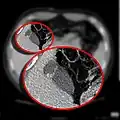

- CT scan showing a phrygian cap

The Phrygian cap results from folding of the gallbladder fundus.

In medicine, a Phrygian cap is the folded portion of some gallbladders that resembles the Phrygian cap (a soft conical cap with the top pulled forward, associated in antiquity with the inhabitants of Phrygia, a region of central Anatolia). It is a normal anatomical variant seen in 1-6% of patients.[1] It is caused by a fold in the gallbladder where the gallbladder fundus joins the gallbladder body.[2] Apart from the chance of being mistaken for stones on a sonogram, it has no other medical implications nor does it predispose one to other diseases. However, due to potential decrease in bile flow, it may warrant a preventive removal of the gallbladder.